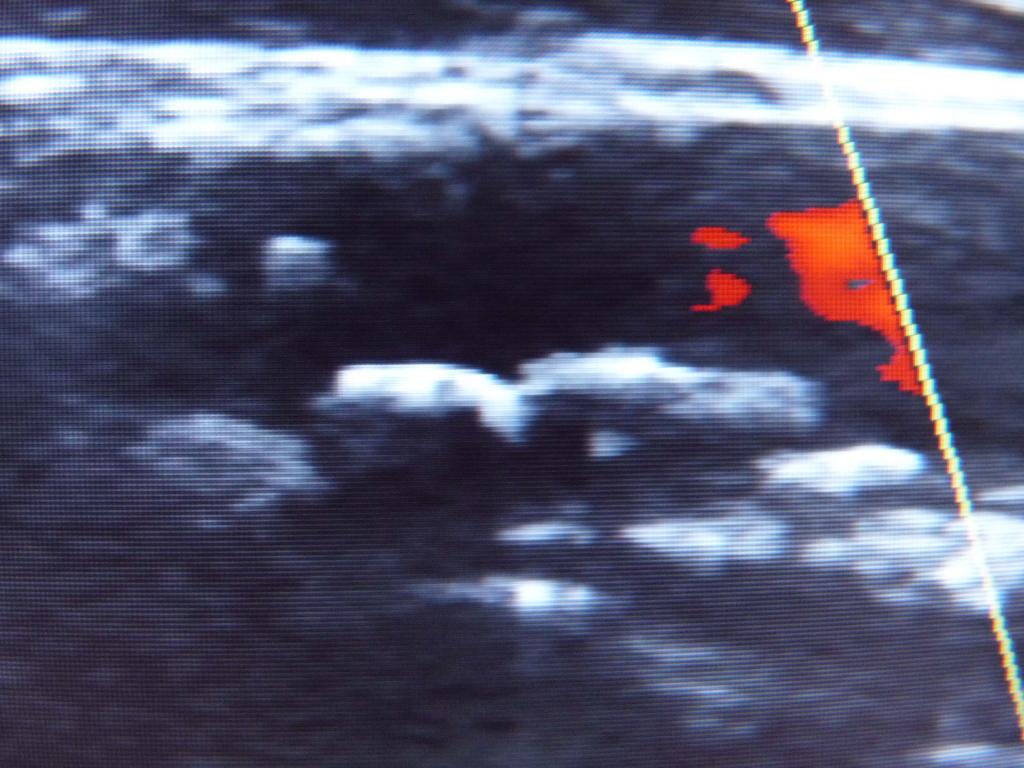

CW-Doppler und Duplexsonographie sind Ultraschallverfahren, mit denen man den Blutfluß in Arterien und Venen darstellen kann. Besonders mit der Farbduplexsonographie lassen sich bereits frühzeitig Cholesterinablagerungen und sich daraus entwickelnde Gefäßverengungen feststellen.